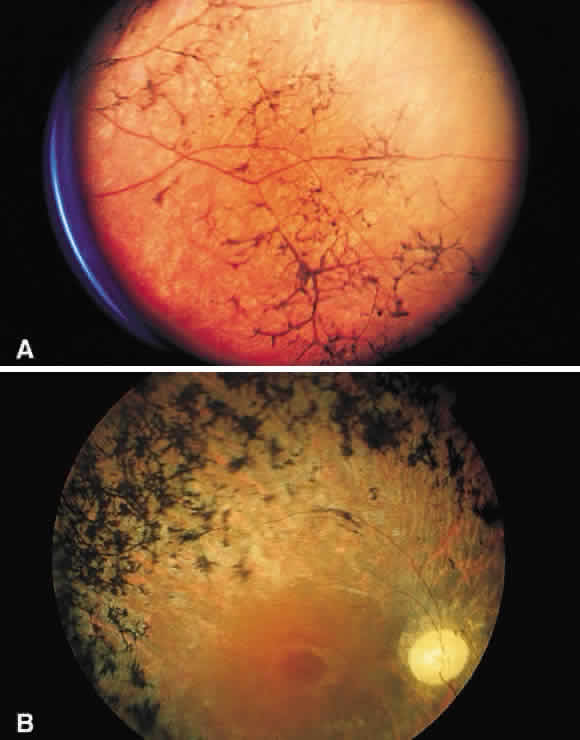

globes is presumed to be derived from metaplastic pigmented epithelium. Pigment epithelial melanin may accumulate within the retina, especially

around retinal vessels (Fig. 50). Because the small retinal vessels branch frequently, the pigment appears

to have the “bone-corpuscular” appearance typically seen

in retinitis pigmentosa (Fig. 51) but also after blunt ocular trauma and intraocular inflammation.  Fig. 50. Photomicrograph of primary retinitis pigmentosa demonstrating pigment accumulation

surrounding a superficial blood vessel and absence of the

rods and cones in the posterior retinal layers. (Courtesy of Ralph C. Eagle Jr, MD, Philadelphia, PA) Fig. 50. Photomicrograph of primary retinitis pigmentosa demonstrating pigment accumulation

surrounding a superficial blood vessel and absence of the

rods and cones in the posterior retinal layers. (Courtesy of Ralph C. Eagle Jr, MD, Philadelphia, PA)

Fig. 51. A. Fundus photograph of retinitis pigmentosa with bone spicule pigmentation. The “bone-corpuscular” appearance is the result of pigment

epithelial melanin accumulation around the small retinal vessel branches. B. Advanced retinitis pigmentosa. There is marked pigment clumping along

with waxy pallor of the disc and attenuated arterioles. Fig. 51. A. Fundus photograph of retinitis pigmentosa with bone spicule pigmentation. The “bone-corpuscular” appearance is the result of pigment

epithelial melanin accumulation around the small retinal vessel branches. B. Advanced retinitis pigmentosa. There is marked pigment clumping along

with waxy pallor of the disc and attenuated arterioles.